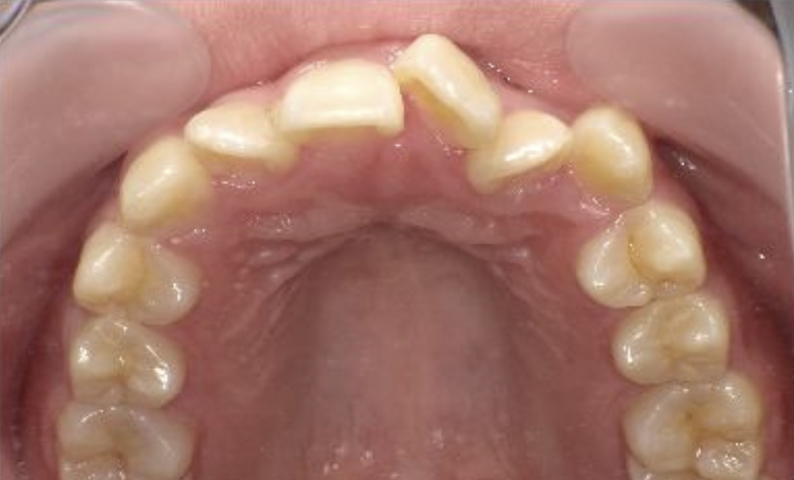

症例_024 上顎だけの部分矯正

治療期間:7ヶ月金額:30万円+税女性前歯のガタガタ上の前歯だけ

| Before | After |